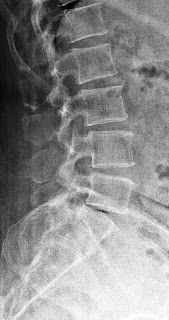

x-rays of normal lumbar spine, and the other two of a patient who had a fixation with pedicle screws and rods.

Lumbar Spondylosis treated with pedicle screw fixation

Lumbar Spondylosis

Lumbar is the medical term for the lower back. Spondylosis is again the term referring to degenerative arthritis of the joints between the bones. Therefore, lumbar spondylosis is arthritis of the back. The back supports the body and helps keep us upright. It is therefore affected by the weight of the body especially when standing, sitting and walking. Pain in the back can radiate to the hips, the legs and the private parts. With pressure on the nerves, it can lead to numbness in the legs and weakness causing difficulty in walking. It can be so bad as to cause problems with passing urine and stool. It can also affect sexual function.

Operations can be designed especially for each patient depending on their particular symptoms, signs and MRI. The operation is done to address the particular problem, be it, back pain, leg pain or both. Pedicle screw fixation is for back pains due to spinal instability.

The following are images of a patient who had had the screws inserted.